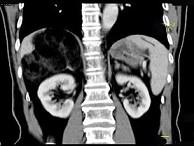

问题 男,59岁,右侧腰背酸痛,CT检查如图所示,应诊断为()

选项 A.右肾上腺腺瘤 B.右肾上腺转移瘤 C.右肾上腺髓样脂肪瘤 D.右腹膜后脂肪瘤 E.右肾血管平滑肌脂肪瘤

答案 C